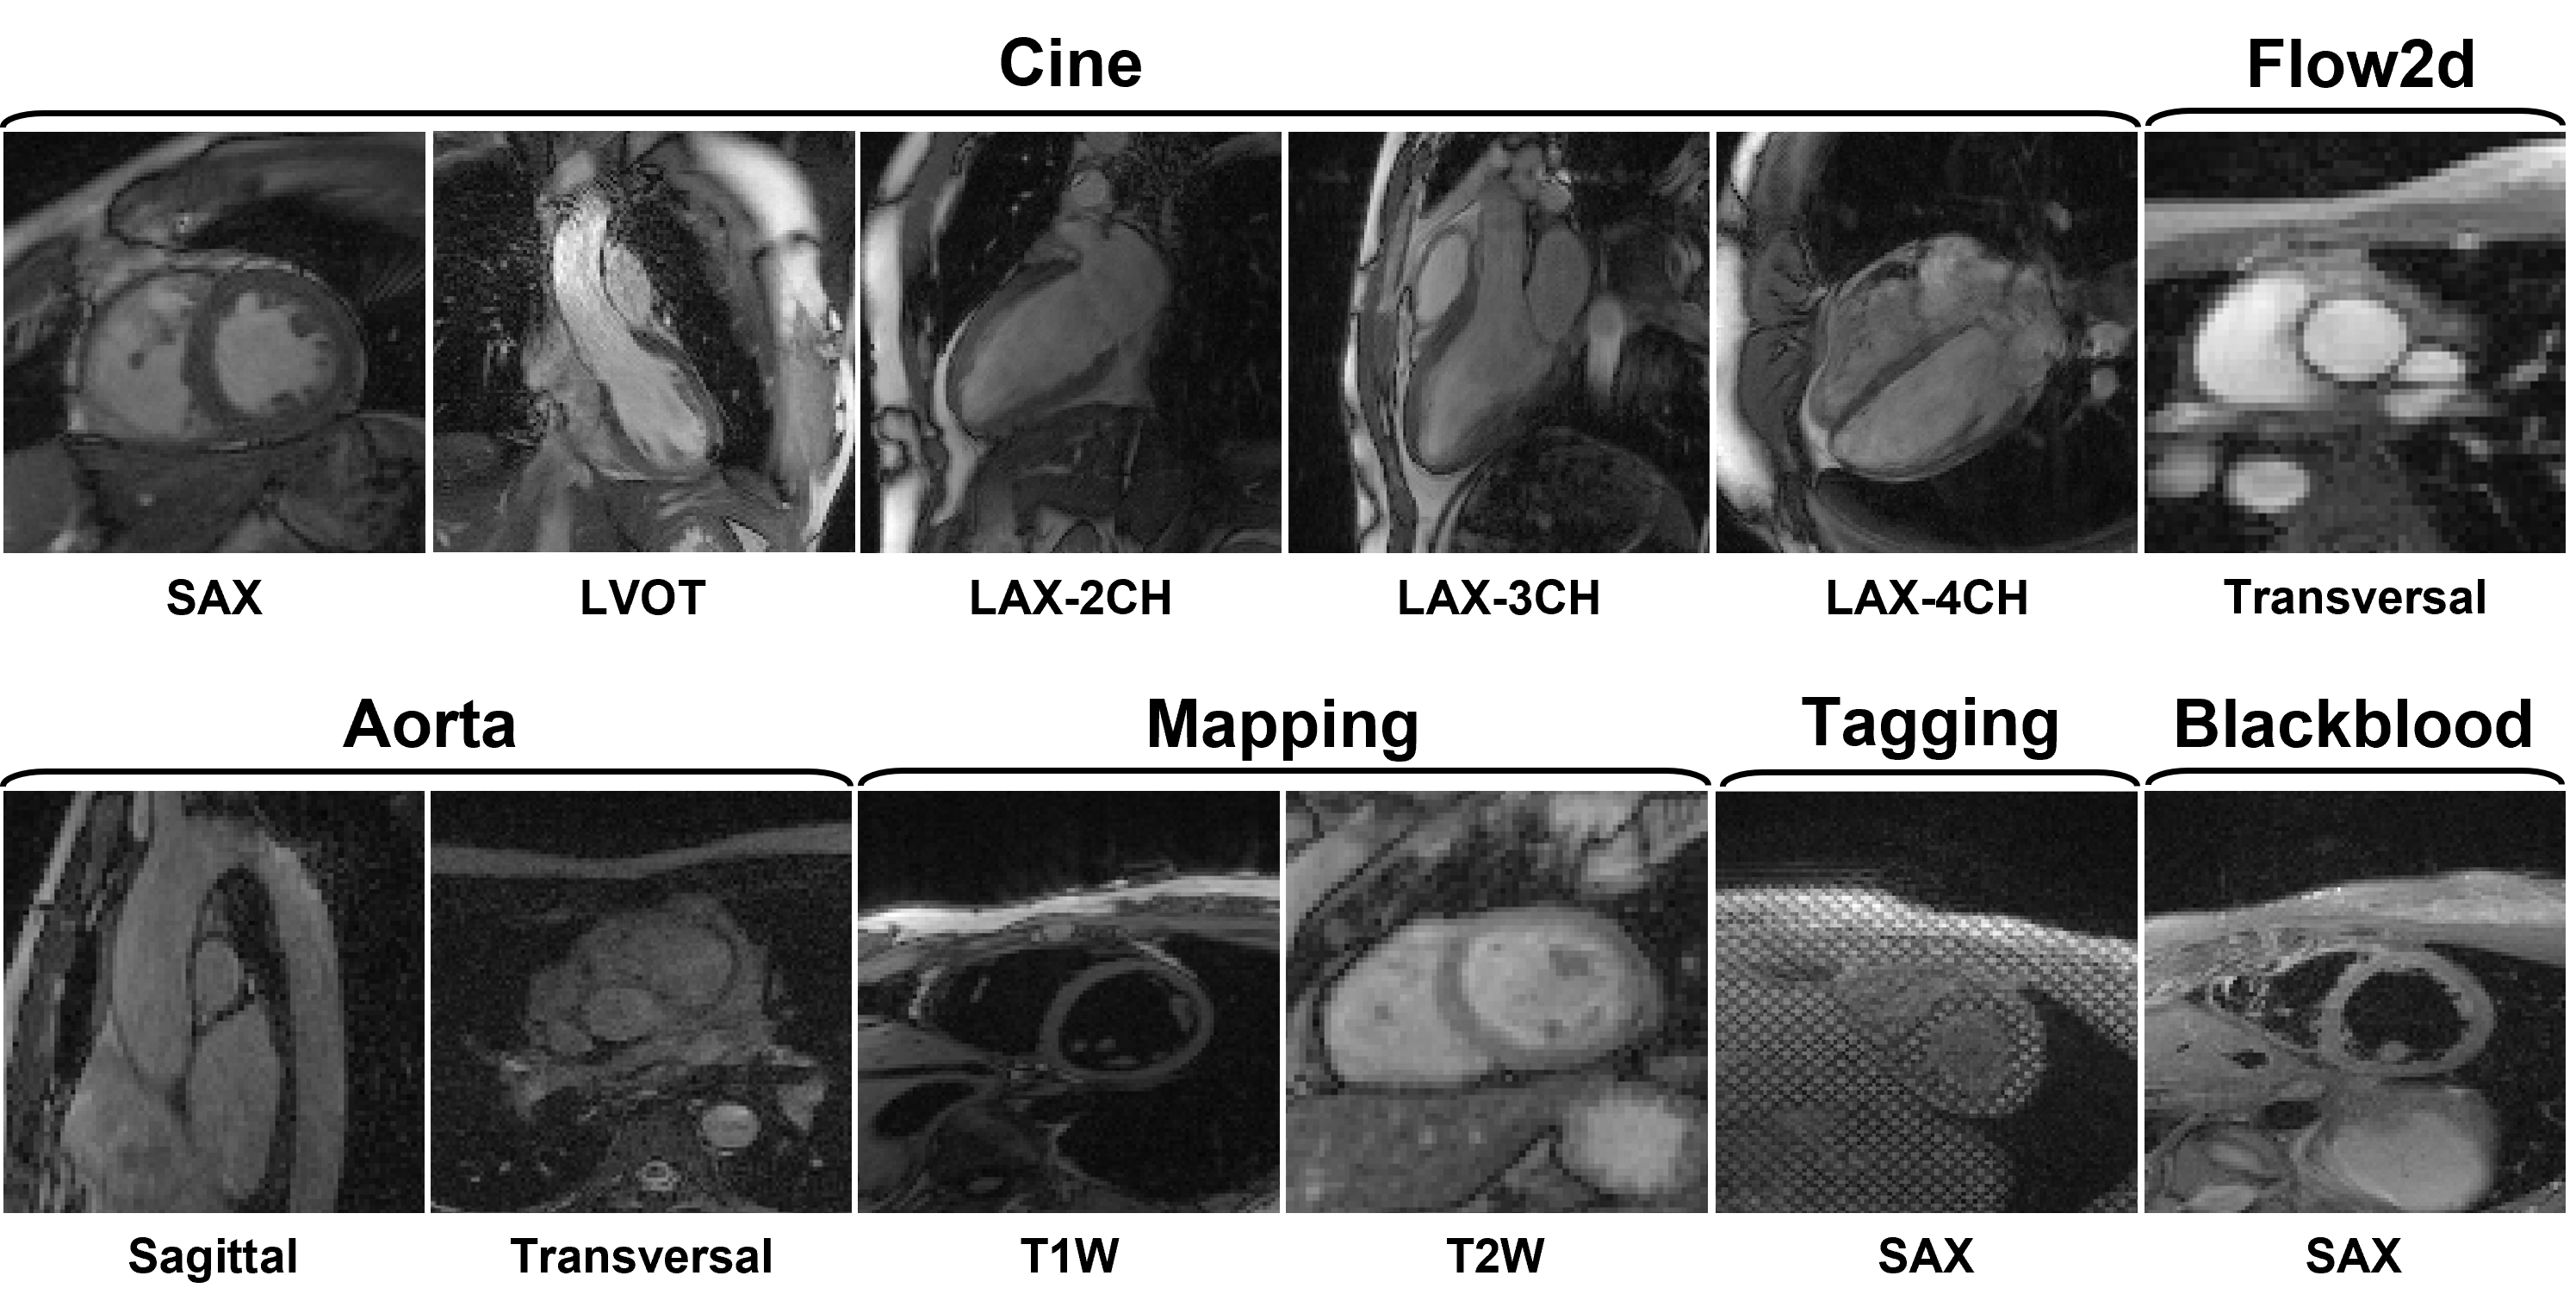

3) Dataset overview: The dataset will include multi-contrast k-space data, consisting of cardiac cine, T1/T2 mapping, tagging, phase-contrast (i.e., flow2d), and dark-blood imaging. It also includes imaging of different anatomical views like long-axis (LAX, including 2-chamber, 3-chamber, and 4-chamber), short-axis (SAX), left ventricul aroutflow tract (LVOT), and aortic (transversal and sagittal views).

4) Scan protocol: We use 'TrueFISP' sequence for cine, phase-constrast (i.e., flow2d), and tagging, and 'FLASH' sequence for T1/T2 mapping and dark-blood imaging. For T1/T2 mapping, signals are collected at the end of the diastole with ECG triggering. Typically, 5~15 slices are acquired for each contrast. The cardiac cycle is segmented into 12~25 phases with a temporal resolution of around 50 ms. Typical geometrical parameters include: spatial resolution 1.5×1.5 mm2, slice thickness 8.0 mm, and slice gap 4.0 mm.